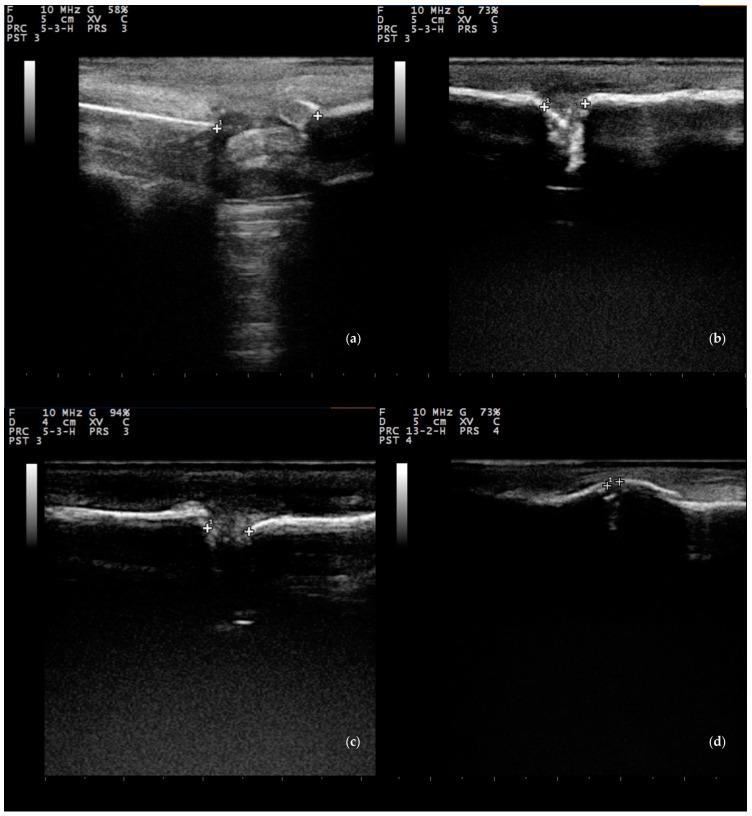

The objectives of the present study were to evaluate (a) the feasibility of using stromal vascular fraction (SVF) and nanocrystalline hydroxyapatite (nHA) paste in combination for the treatment of segmental bone defect, (b) the quality of the callus produced, (c) the potential improvement of the autograft technique, and (d) the direct comparison of the biomaterial to the use of autogenous cancellous bone. Unilateral, segmental mid-diaphyseal bone defect was created on the right metatarsus of skeletally mature sheep animals ( = 24) under anesthesia (D0). Residual segments were stabilized by stainless-steel plates and appropriate screws. Defects were managed as follows: group A: use of nHA paste to filling, group B: use of autogenous bone graft mixed with nHA bone paste, placed in defect, group C: use of SVF mixed with nHA bone paste injected into defect, group D: use of bone graft and SVF with nHA paste before apposition in bone defect. SVF had been previously isolated from adipose tissue of the animals intra-operatively after digestion with collagenase solution and neutralization. Animals were evaluated clinically and by X-raying and ultrasonographic examination of the defect, at regular intervals, until D90. Ultrasonographic assessment performed along the length of the defect included calculation of the length of the bone defect and assessment of vascularization. SVF was successfully isolated from group C and D animals, with the average yield being 1.77 × 10 cells. The comparison of clinical scores (based on the 'Kaler scale') on each post-operative day indicated significant differences between the four groups on D1 to D30 ( < 0.01); the median clinical score within group A was 2.5 for D1-D30 and 1 for the entire period; respective scores for other groups were 1.5 ( = 0.07) and 0 ( = 0.033). Differences in radiographic assessment scores were significant for scores obtained on D60 ( = 0.049) and D90 ( = 0.006). There was a significant difference between the four groups in the length of the bone defect, as assessed ultrasonographically, for the entire length of the study; median values were 8, 8.5, 6, and 8 mm for groups A, B, C, and D, respectively ( = 0.008). There was a significance in the differences between median scores obtained during the histopathological examination: 2, 11, 13.5, and 12 for group A, B, C, and D ( = 0.022). There was an inverse correlation between the overall scores of histopathological evaluations and the length of the bone defect (observed on D90) ( < 0.0001) and a correlation between the overall scores and the radiographic assessment scores (obtained on D90) ( < 0.0001). This is the first study in which the efficacy of fresh autologous Stromal Vascular Fraction (SVF) from adipose tissue in enhancing bone healing in a long, weight-bearing, diaphyseal bone was evaluated. It is concluded that the lumbosacral region was an attractive site for harvesting adipose tissue, the use of SVF contributed to faster rehabilitation post-operatively, and SVF significantly enhanced bone formation; in general, the results indicated an osteogenic potential of SVF comparable to the gold standard autologous bone graft.

(a)联合使用基质血管成分(SVF)和纳米晶羟基磷灰石(nHA)糊剂治疗节段性骨缺损的可行性;(b)所产生骨痂的质量;(c)自体移植技术的潜在改进;(d)将该生物材料与自体松质骨的使用进行直接比较。在麻醉下(D0),在骨骼成熟的绵羊动物(n = 24)的右跖骨上制造单侧、节段性骨干中部骨缺损。残余节段用不锈钢板和合适的螺钉固定。骨缺损的处理如下:A组:使用nHA糊剂填充;B组:使用自体骨移植混合nHA骨糊剂,置于缺损处;C组:使用SVF混合nHA骨糊剂注入缺损处;D组:在骨缺损对接前使用骨移植和含nHA糊剂的SVF。SVF先前已在术中用胶原酶溶液消化并中和后从动物的脂肪组织中分离出来。定期对动物进行临床评估,并对缺损部位进行X线和超声检查,直至D90。沿缺损长度进行的超声评估包括计算骨缺损的长度和评估血管化情况。在C组和D组动物中成功分离出SVF,平均产量为1.77×10⁶个细胞。术后每天的临床评分(基于“Kaler量表”)比较表明,在D1至D30期间,四组之间存在显著差异(P < 0.01);A组在D1 - D30的临床评分中位数为2.5,整个期间为1;其他组的相应评分为1.5(P = 0.07)和0(P = 0.033)。在D60(P = 0.049)和D90(P = 0.006)获得的放射学评估评分存在显著差异。在整个研究期间,通过超声评估,四组在骨缺损长度方面存在显著差异;A、B、C和D组的中位数分别为8、8.5、6和8 mm(P = 0.008)。组织病理学检查获得的中位数评分之间存在显著差异:A、B、C和D组分别为2、11、13.5和12(P = 0.022)。组织病理学评估的总体评分与骨缺损长度(在D90观察到)之间存在负相关(P < 0.0001),与放射学评估评分(在D90获得)之间存在相关性(P < 0.0001)。这是第一项评估来自脂肪组织的新鲜自体基质血管成分(SVF)在促进长的、负重的骨干骨愈合方面疗效的研究。得出的结论是,腰骶部是采集脂肪组织的理想部位,SVF的使用有助于术后更快康复,且SVF显著增强骨形成;总体而言,结果表明SVF的成骨潜力与金标准自体骨移植相当。